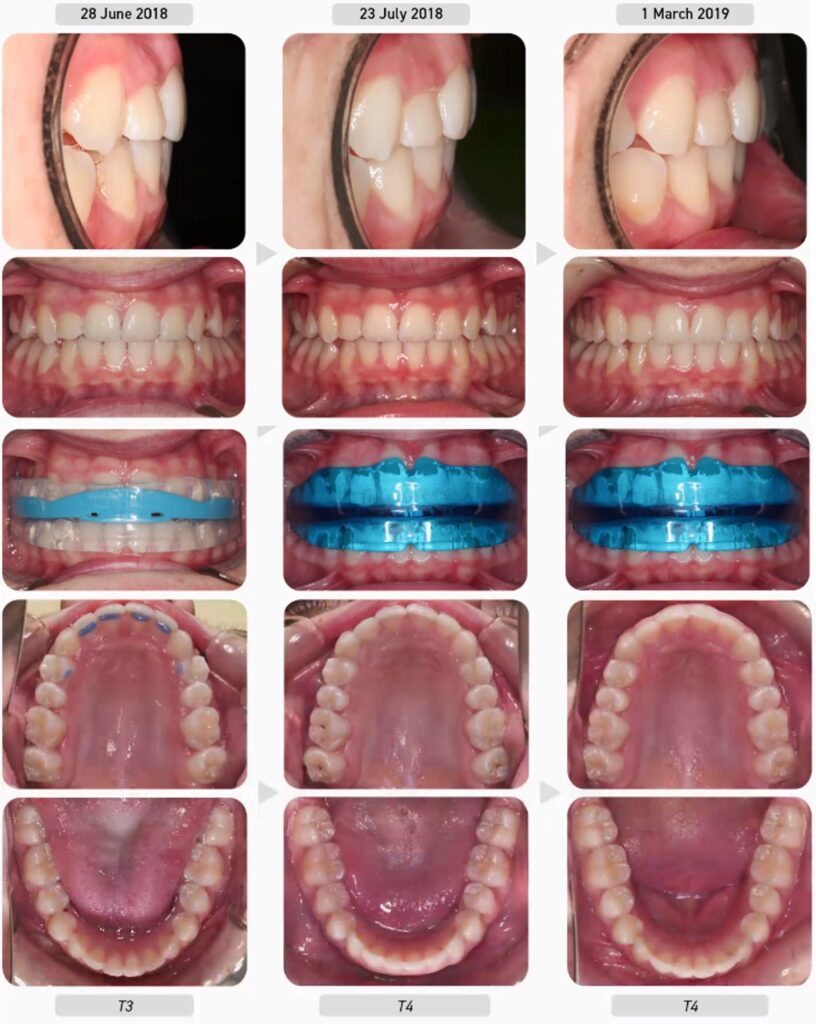

Lưu ý rằng sau hai tháng rưỡi nới rộng với BWS, các R6 hàm trên bắt đầu di xa. Khi điều này xảy ra, dây cung sẽ được tháo ra để răng cối lớn ổn định trở lại và bệnh nhân được cho đeo lại khí cụ K2. Hai tháng sau, bệnh nhân đã sẵn sàng bước vào đợt nới rộng BWS thứ hai để phát triển hàm trên hơn nữa và cải thiện chức năng nên K1 đã được cấp lại. Ba tháng sau, quá trình nới rộng BWS hoàn tất và bệnh nhân được cấp khí cụ T2.

Lưu ý overjet tăng nhẹ sau mỗi lần nới rộng với BWS. Điều này là thuận lợi vì nó cho phép hàm dưới lùi dần về phía trước khi cung hàm trên phát triển.

Sau khi cung răng đã phát triển đẹp và các thói quen cơ chức năng của bệnh nhân đã được sửa chữa phần lớn, bệnh nhân chuyển sang đeo khí cụ T3 để sắp đều răng hơn và cuối cùng là đeo khí cụ T4 để duy trì. Chín tháng sau, chúng ta có thể thấy răng bệnh nhân vẫn ổn định mà không cần bất kỳ hình thức duy trì cố định nào.

Điều quan trọng cần lưu ý là trong điều trị Myobrace®, chúng ta không quan tâm đến sự thẳng đều răng hoàn hảo mà là đạt được sự thẳng hàng tự nhiên của răng kết hợp với việc điều chỉnh thói quen. Một khi mục tiêu điều trị Myobrace® đã đạt được đã đạt được (thiết lập thở mũi, điều chỉnh các thói quen cơ chức năng và đạt được hình dáng cung răng tốt), bệnh nhân bước vào giai đoạn duy trì với khí cụ T4.